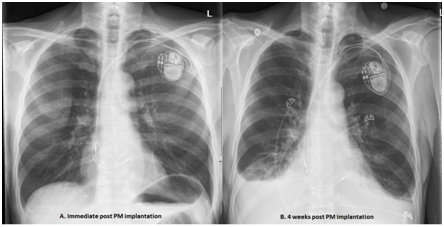

A 74-year-old male presented with symptoms of pre-syncope, shortness of breath and fatigue. His past medical history was significant for known right bundle branch block, gastroesophageal reflux disease, allergic rhinitis and chronic constipation. A 48 Holter monitor revealed type 2second degree atrioventricular (AV) block. On 01/14/2015, he underwent placement of a Medtronic dual chamber permanent pacemaker without any apparent complications. Postoperative device interrogation and chest x-ray were normal; Hb was 13.5g/dl. On 01/30/2015 he presented with sudden onset of racing heart and presented to the ER with atrial fibrillation with rapid ventricular response, he converted to sinus rhythm with intravenous Diltiazem. Transthoracic Echocardiogram (TTE) showed small pericardial effusion but was otherwise normal Four weeks later on 02/12/2015, he presented with right sided pleuritic chest pain and shortness of breath. He also reported occasional palpitation but no fever, chills, cough, syncope, leg swelling or joints pain. His vital signs were stable. Physical examination was remarkable for a soft pericardial friction rub and diminished breath sounds at the lung bases. Laboratory data showed mild leukocytosis (WBC: 12.8k/ul), CRP: 12.9mg/dl (normal<1mg/dl) and ESR: 64mm/h. A 12-lead ECG showed sinus rhythm with atrial tracking ventricular pacing and right bundle branch bock pattern in V1 (Figure 1). A chest x-ray revealed bilateral pleural effusion and confirmed that both leads were in appropriate positions (Figure 2). TTE revealed a moderate sized pericardial effusion with no echocardiographic finding of tamponade physiology (Figure 3).

Figure 2 A 12-lead ECG showed sinus rhythm with atrial tracking ventricular pacing and right bundle branch bock pattern in V1.

However, an immune mediated inflammatory response to initial cardiac injury triggered by pacemaker lead may play a role on the pathogenesis of this syndrome.2 Advanced age, female gender and the use of active fixation leads are independent risk factors for the development of post pacemaker insertion pericarditis.5 The clinical manifestations are characterized by pleuritic chest pain, fever and elevated acute phase reactants, pericardial effusion and/or pleuritis with or without pleural effusion. Most of these patients present within one month after the index procedure. Physical examination may reveal distant heart sounds, pericardial or pleural rub and signs of pleural effusion. Chest x ray and echocardiogram confirms the presence of pleural and/or pericardial effusion as well as leads position. Overt or micro lead perforation is an important differential diagnosis and a well-known complication of pacemaker implantation.6